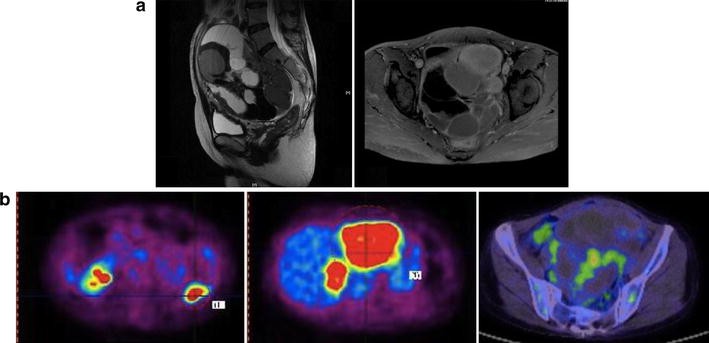

PET–CT and MRI images 1 month after onset. a MRI images of the pelvic tumor. Mixtures of diverse intensities ranging from low to high, suggesting a variety of liquid and solid components, are seen. There seems to be a hemorrhage and mucus in it. Strong enhancement is seen in the cyst wall. A multilocular cystic ovary including a metastatic lesion of cyst walls with contrast enhancement was possibly suggested. b Axial PET–CT fusion images of the colon, liver, and ovary. SUVmax values of 9.0 in the colon, 7–10.0 in the liver, and 4.0 in the ovary were detected